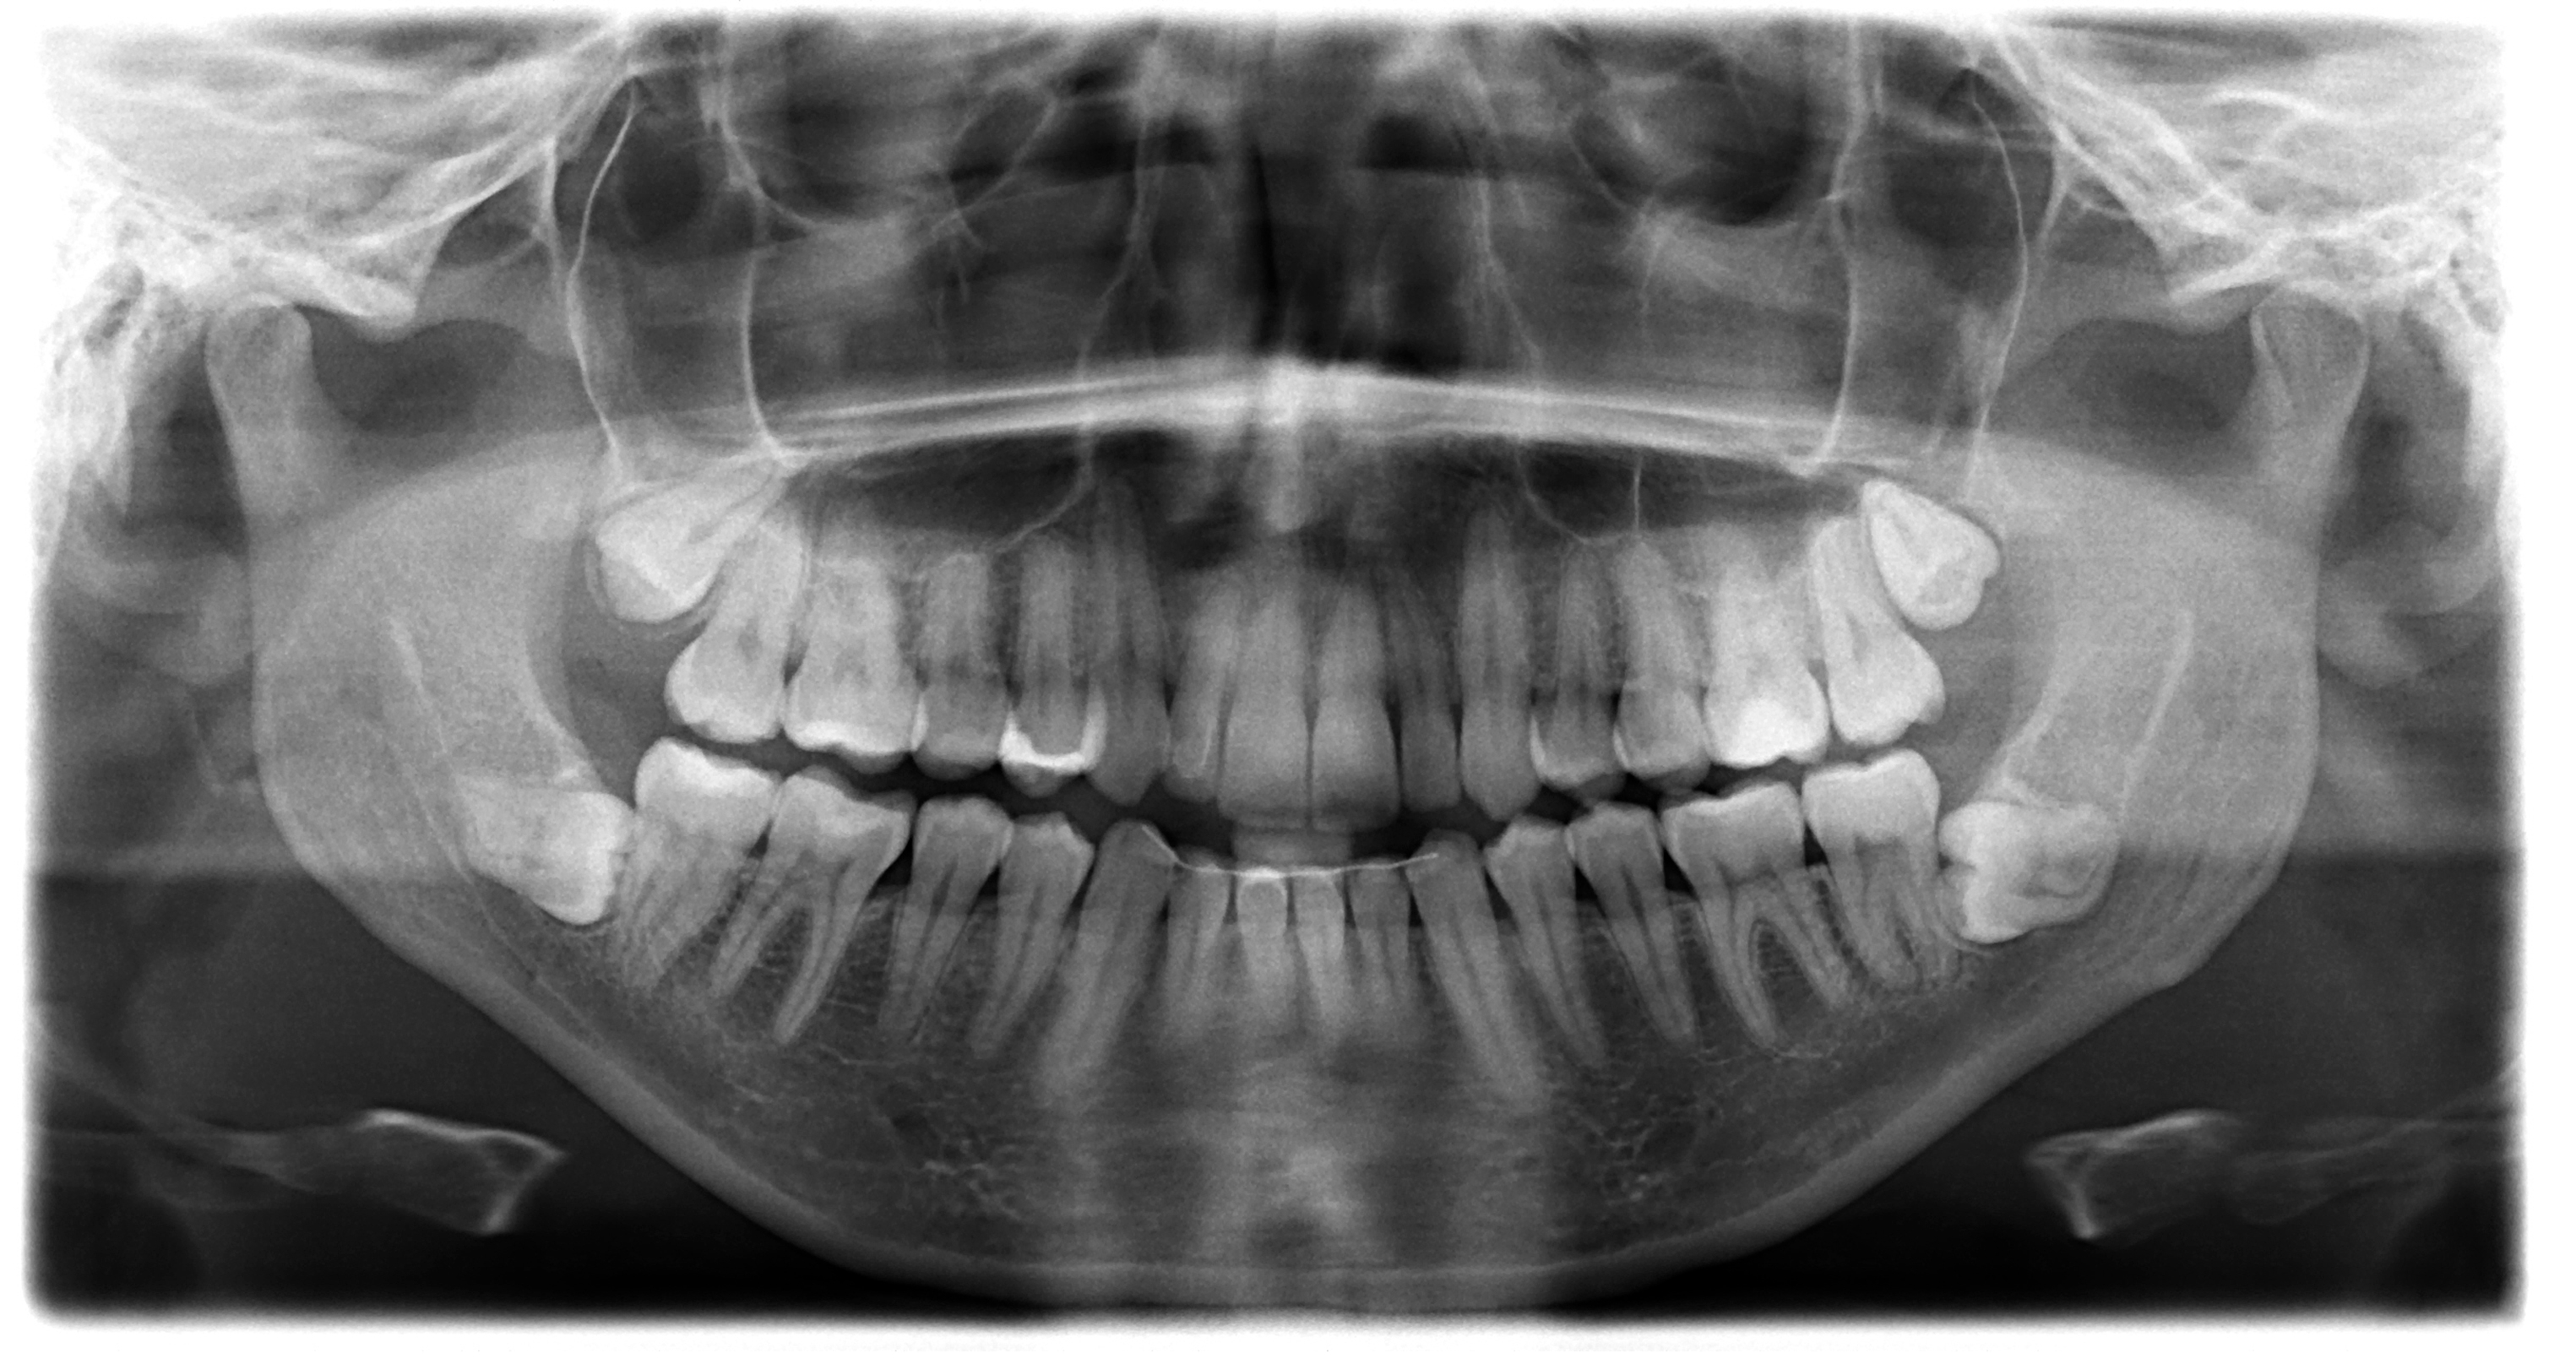

Čovek uradio rendgenski snimak zuba, stomatolozi ostali u šoku: Prizor oborio Ginisov rekord

Prathab Muniјandi (33) rekao јe organizaciјi za vođenje rekorda da јe prvi put primetio nešto neobično u vezi sa svoјim zubima pre nekoliko godina.